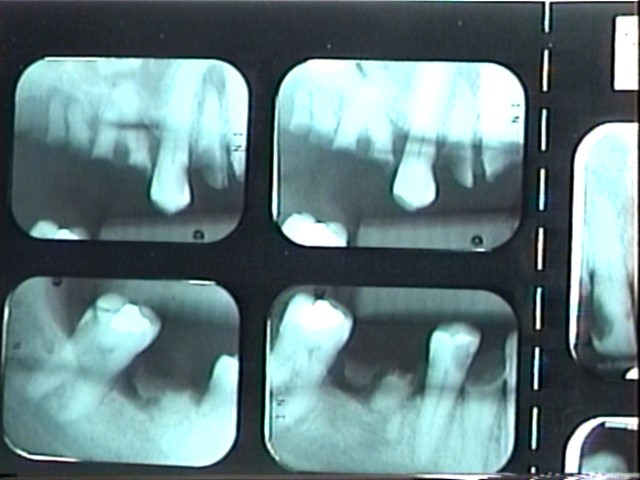

Fig 12. Radiographs of patient in Fig 10 and Fig 11 illustrating nonrestorability of the dentition.

Figure 12